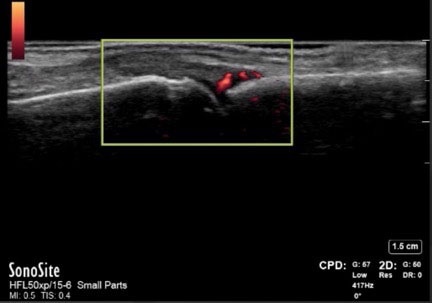

Hand MCP Joint Synovitis Early RA Seronegative Image